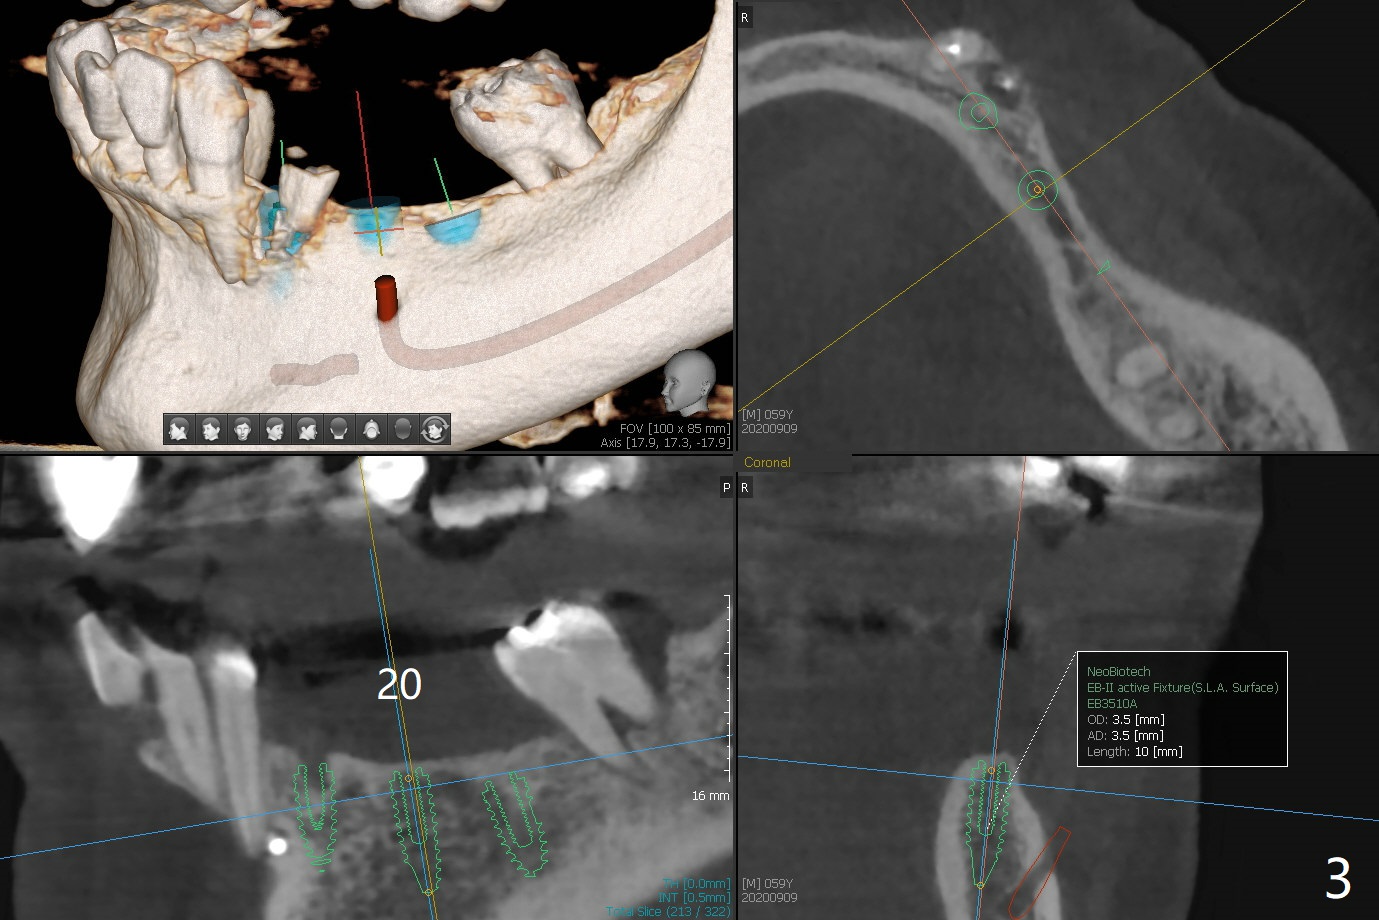

A 59-year-old woman has an abscess buccal to #21 (residual root), immediate placement being imminent, while the teeth #19 and 20 have been missing for a while. Since the ridge is narrow even at #21, three narrow implants will be placed at these sites (Fig.1-3). Please place an implant as close to the lingual (L) plate (but not to touch it to avoid deviation during placement) at #21 (Fig.1).